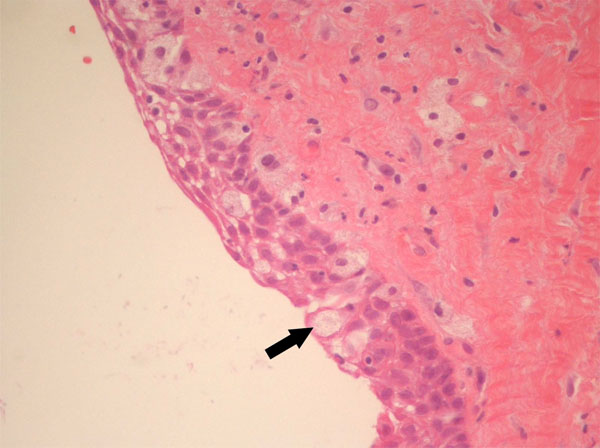

In October 2011, a 38-years-old woman was admitted at the University Hospital “Ospedali Riuniti” in Ancona, Italy, with a radiolucent lesion in the anterior mandible. The lesion was asymptomatic and was discovered as an incidental finding by a dentist some months before. The patient’s medical history was not significant. Oral examination showed normal appearance and color of mucosa. Radiographic examination showed a well-defined, unilocular lesion extending in the left mandible anterior body (Fig. 1). The lesion was extended in an intraradicular position, with superior limits ranging between the roots of the canine and the first and second premolar. The teeth were all vital. The lesion was subjected to surgical enucleation, and the material was sent for histopathological examination. Histological analysis of the lesion revealed a cyst wall with focally ciliated epithelium lining of variable thickness. The superficial layer of the epithelium showed metaplastic mucous cell with intraepithelial microcystic area (Fig. 2, 3 and 4). The results of immunohistochemistry revealed strong positive activity for CK 19 in all layer of the epithelium (Fig. 5). The final diagnosis was glandular odontogenic cyst. The postoperative course was uneventful. Intraoral examination and radiographic evaluations by OPT every 6 months showed no recurrence during the 12 months follow-up period.

High magnification of mucous cells (x40).